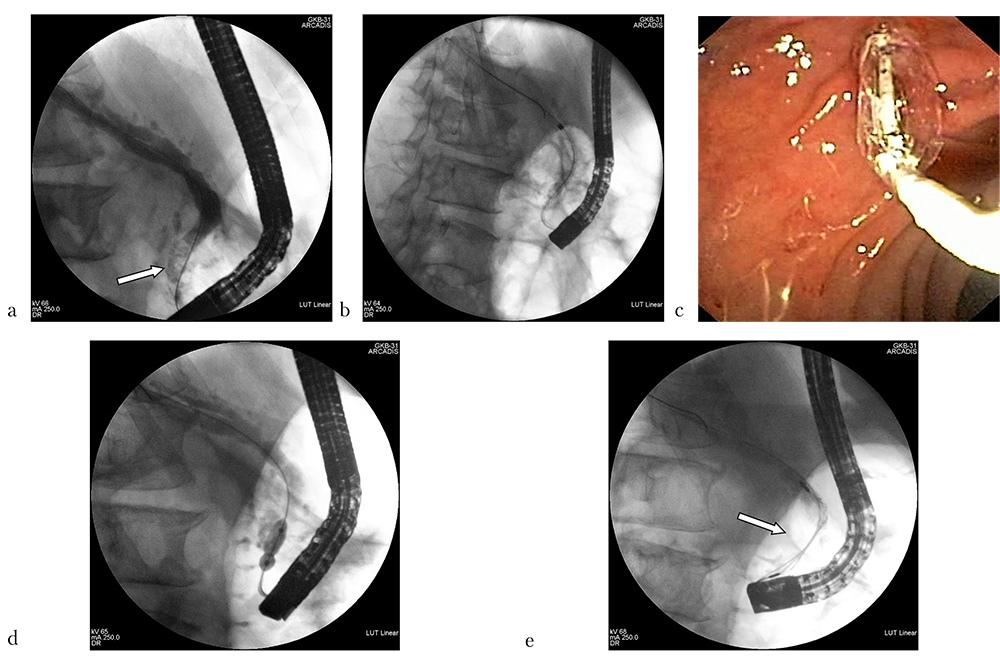

Первым этапом эндоскопического лечения было проведено удаление инкрустированного панкреатического стента, ретроградная панкреатикография, по результатам которой было выявлено относительное сужение ГПП в терминальном отделе до 2–3 мм на протяжении 3–4 мм, что, вероятнее всего, являлось одним из проявлений хронического панкреатита и пусковым механизмом развития ВЛ. Также на расстоянии около 1 см от устья ГПП визуализирован конкремент неправильной овальной формы с неровными краями размерами 18ђ12 мм (рис. 8a). Нами была выполнена дополнительная ВТ, бужирование зоны сужения терминального отдела вирсунгова протока механическими дилататорами Soehendra от 4 до 9 Фр фирмы Cook (США) и дополнительная баллонная дилатация области вирсунготомии и панкреатической стриктуры с помощью дилатационного баллона диаметром 6–8 мм и длиной 2 см фирмы Boston Scientific (США) (рис. 8b–d). После этого были предприняты многочисленные попытки захвата вирсунголита с целью проведения его внутрипротоковой механической литотрипсии, которые, однако, оказались безуспешны по причине невозможности проведения литотриптора выше камня (рис. 8e). В связи с этим была проведена диагностическая пероральная транспапиллярная панкреатикоскопия с целью визуального осмотра конкремента и оценки технической возможности выполнения лазерной литотрипсии. При визуальном изучении вирсунголита выяснено, что он занимает практически весь просвет ГПП, имеет неровные, шероховатые края и выраженно плотную структуру (рис. 9a). Учитывая размеры, локализацию и наличие адекватного доступа к конкременту, было принято решение о целесообразности проведения контактной лазерной литотрипсии с использованием нового суперимпульсного фиброволоконного тулиевого лазера.

Рис. 8: a — выраженно расширенный ГПП с конкрементом в проекции головки ПЖ — конкремент указан стрелкой (панкреатикограмма); b — бужирование ГПП механическим дилататором (панкреатикограмма); c — баллонная дилатация устья и терминальных отделов ГПП (эндофото); d — баллонная дилатация стриктуры терминальных отделов ГПП (панкреатикограмма); e — попытка механической литотрипсии, при которой отмечена техническая невозможность захвата вирсунголита, конкремент — указан стрелкой (панкреатикограмма)